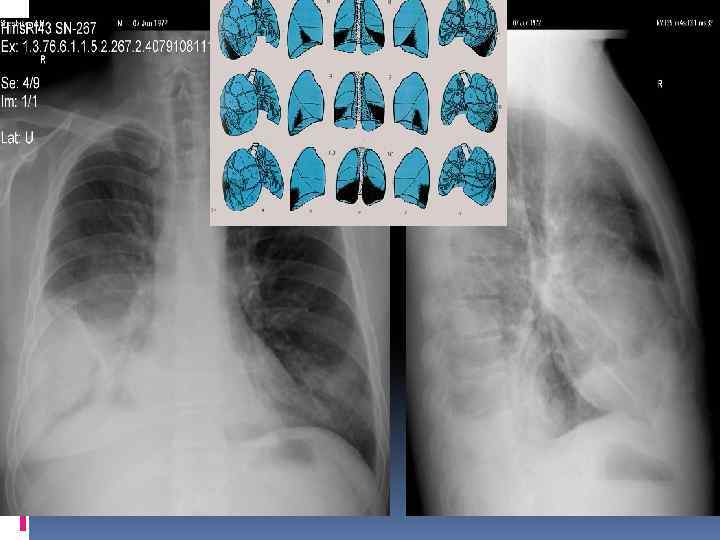

Легкие. Проекция долей легких. Правое легкое: две междолевые щели делят легкое на три доли. Левое легкое имеет две доли Пространственное расположение междолевых щелей. Топография долей легкого.

Анатомия ОГК. Пневматизация. Плевра. Междолевые борозды.

Междолевые борозды. Борозда между нижней и верхней, средней долями справа и верхней и нижней долями слева - главная междолевая борозда, имеется с обеих сторон. Справа между верхней и средней долями расположена дополнительная, малая горизонтальная междолевая борозда. Борозды бывают неполными, могут встречаться дополнительные борозды, образующие доли. Борозда состоит из двух слоев плевры, между которыми имеется потенциальная щель. В месте перехода грудной стенки в диафрагму, слои плевры образуют острый угол – синус (заворот): реберно диафрагмальный, реберно – медиастинальный. Задние реберно-диафрагмальные синусы самые глубокие, вытянуты в каудальном направлении.

Междолевые борозды.